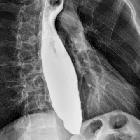

Achalasia characteristically involves a short segment (less than 3.5 cm in length) of the distal esophagus.

Fluoroscopy with barium swallow

A barium swallow study may be used to confirm esophageal dilatation, in addition to assessing for mucosal abnormalities.

Findings include:

- bird beak sign or rat tail sign

- esophageal dilatation